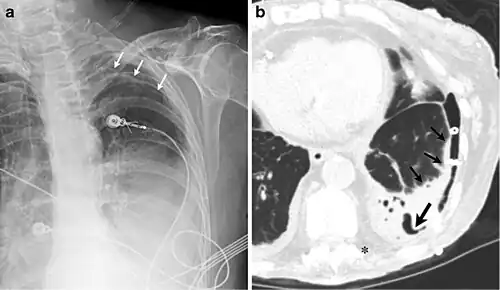

- Zwei Röntgenbilder zur Pleuraschwarte